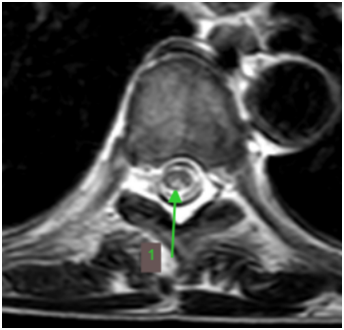

半年前,王先生開始感覺走路不穩(wěn),像踩在棉花上,還伴有肢體麻木無力。這些癥狀逐漸加重,最終他來到鄭州大學(xué)第五附屬醫(yī)院神經(jīng)內(nèi)科二病區(qū)就診。檢查發(fā)現(xiàn),他患有巨幼紅細胞性貧血,維生素B12水平明顯偏低。脊髓磁共振結(jié)果顯示:胸段脊髓后索出現(xiàn)異常高信號(如圖黃色箭頭所示),軸位圖上更是呈現(xiàn)出典型的倒“V”征(綠色箭頭)。